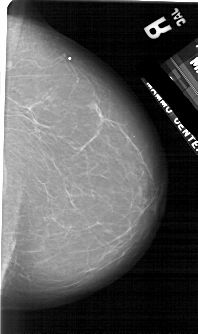

A_1754_1.RIGHT_MLO

RIGHT_MLO LINES 5281 PIXELS_PER_LINE 3226 BITS_PER_PIXEL 12 RESOLUTION 43.5 NON_OVERLAY